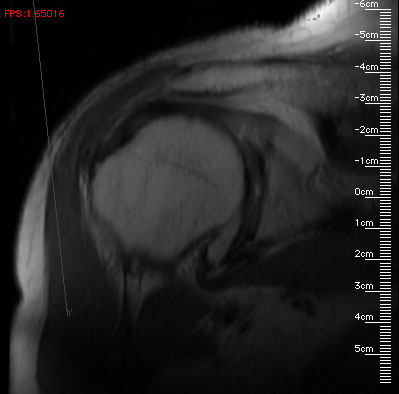

The program presents the user with two windows-- the smaller window has zoom and translation controls, and the larger window serves as both the output window and allows the user to easily and interactively rotate the block of data. I use an interactive rotation input system similar to the Volrend system's [Standish, 1995] virtual trackball. An actual screen image from the program is below.

The images have rulers which display millimeter distances, matched to the zoom factor. If the user drags the mouse inside the image window (labeled "Slice 3D") the block of data rotates beneath the mouse. If the user clicks the mouse in the image window, the program computes the 3D coordinates (in millimeters) of the clicked point on the slicing plane, and writes them to standard output. These coordinates could then be captured to a file and passed to another program for further analysis (e.g., for MRI geometric calibration, estimating the volume of a lesion, or planning a minimally harmful path for radiation treatment).